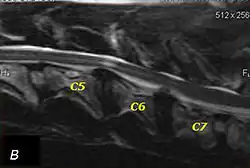

Doberman C6-C7 and C5-C6 traction responsive myelopathy A

Doberman C6-C7 and C5-C6 traction responsive myelopathy B

T2 weighted MRI in neutral (A) and linear traction (B) of a seven-year-old Doberman with a two-year history of cervical pain treated with NSAIDs and presented acutely tetraplegic: A C6-C7 and C5-C6 traction responsive myelopathy are evident on MRI. The spinal-cord hyperintensity seen at the C5-C6 is suggestive of chronic lesion and most likely responsible for the chronic history of cervical pain, while the C5-C6 lesion was most likely responsible for the acute tetraplegia.